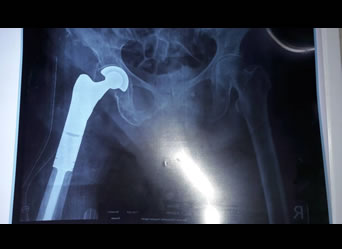

Proximal Femoral Endoprosthetic Replacement

Proximal femoral endoprosthetic replacement | total hip replacement | total knee replacement distal femoral endoprosthetic replacement